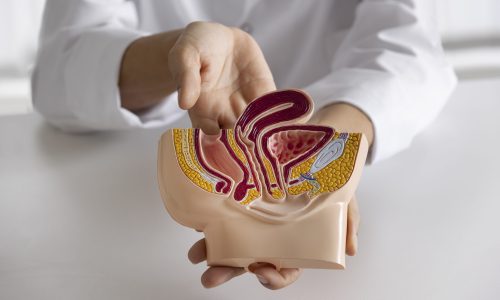

What Are Piles & Fistula?

🔹 Piles (Arsha) – Swollen, inflamed veins in the anal region. Can be internal or external.

🔹 Fistula-in-Ano (Bhagandara) – An abnormal channel between the anal canal and the skin, often filled with pus or fluid.